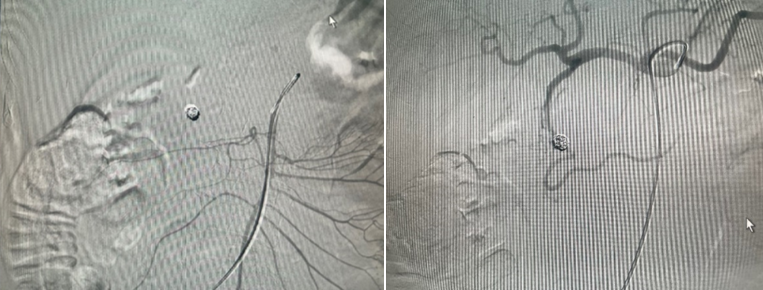

- Đến 8h ngày 27/12:  bệnh nhân lại nôn ra máu tươi, huyết áp dao động 80/40 – 90/50, mạch 120 lần/phút. Bệnh nhân được chỉ định chụp mạch tạng (DSA). Kết quả chụp mạch có 1 túi giả phình nằm ở 1 nhánh của động mạch vị tá tràng đang chảy máu. Bệnh nhân được can thiệp nút túi giả phình này. Sau can thiệp bệnh ổn đinh, theo dõi đên ngày 03/01/2023 bệnh nhân huyết động ổn, không nôn, ăn uống được, xét nghiệm công thức máu ổn. Bệnh nhân được ra viện cùng ngày, sau ra viện ổn.

Hình 5 và 6. Chụp mạch trước can thiệp